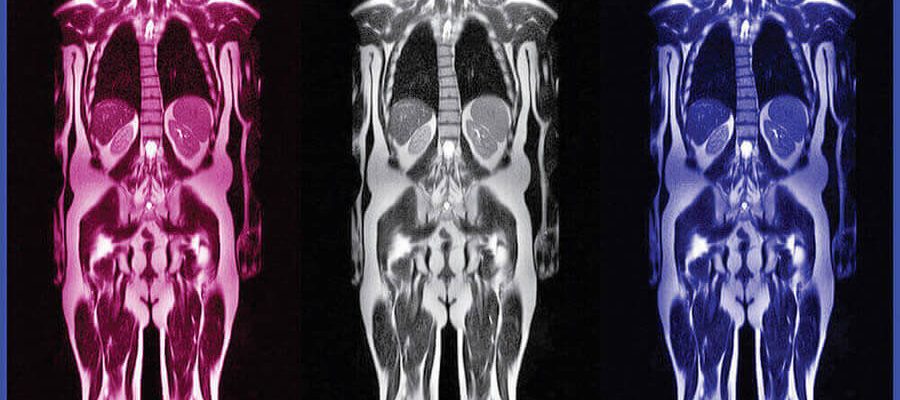

Tüm vücut mr, tehlikeli bir durum ile karşı karşıya kalmadan, radyasyonsuz bir şekilde gerçekleştirilir. Tümörlerin erken evrede fark edilebilmesi ya da teşhisini koyabilmek için manyetik rezonans görüntüleme yapılır. Bu görüntüleme tekniği sayesinde tüm vücuda çekim yapılır.

Sayılı noktaların gerçekleştirmiş olduğu bu görüntüleme tekniğini Galenlab laboratuvar hizmetleri tarafından sağlanabilir. Bütün vücut için ayrı çekimler gerçekleştirilir ve daha sonra birleştirilerek tek parça haline getirilmiş olur.

Tüm vücut mr tarama farklı organ ve bölgelere yapıldığı için diğer emar uygulamasına göre biraz daha zaman alabilir. Parça parça şekillerde işlem yapılır ve daha sonra tek parça haline getirilir. Çekim süresi hakkında kesin bilgi vermek mümkün değildir.